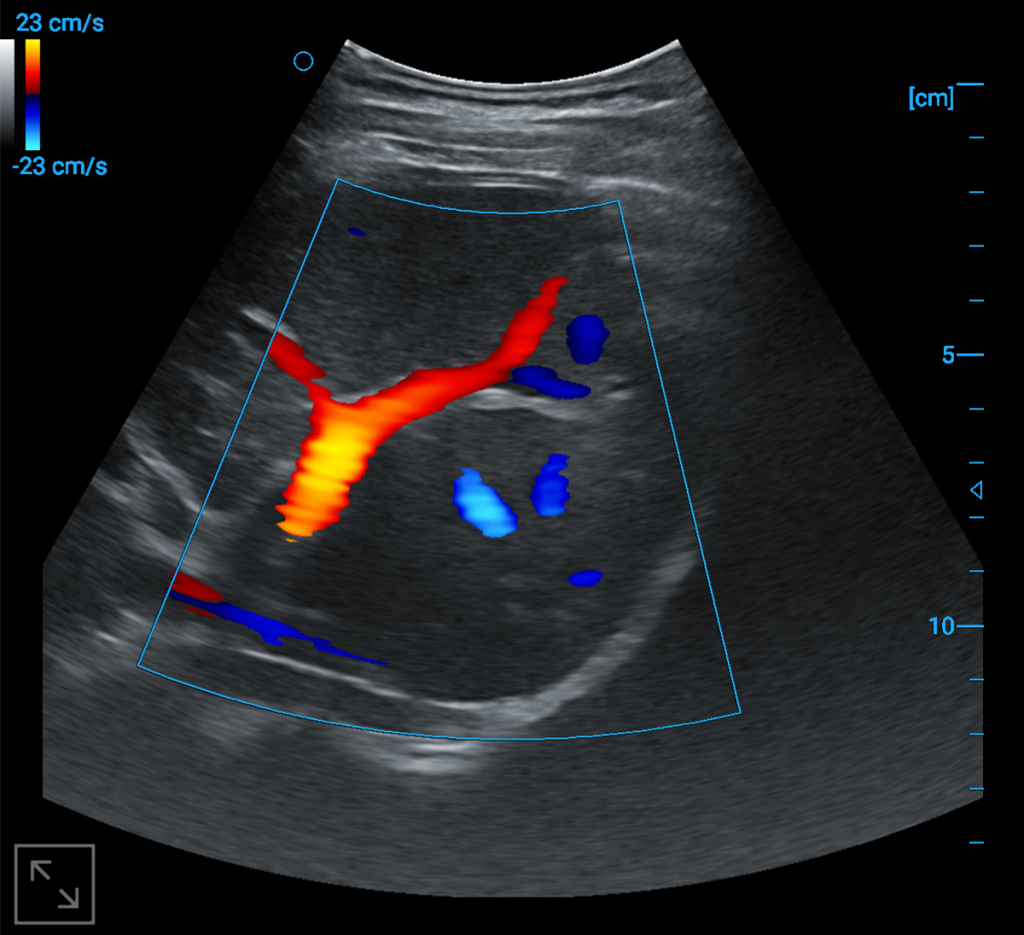

Liver blood flow

wireless images

Kindey blood flow